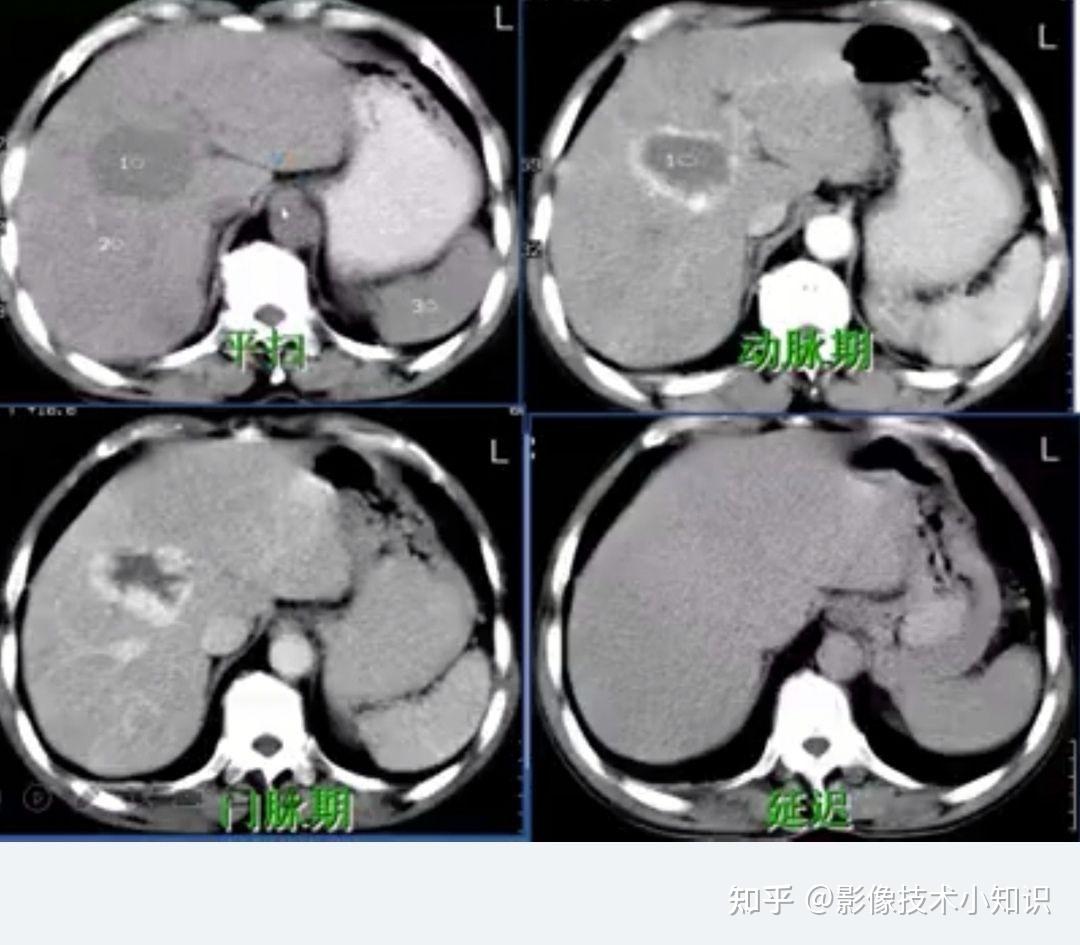

一图学习肝囊肿,血管瘤,转移瘤,fnh,肝腺瘤,肝癌的mr影像表现

图片尺寸1080x1290